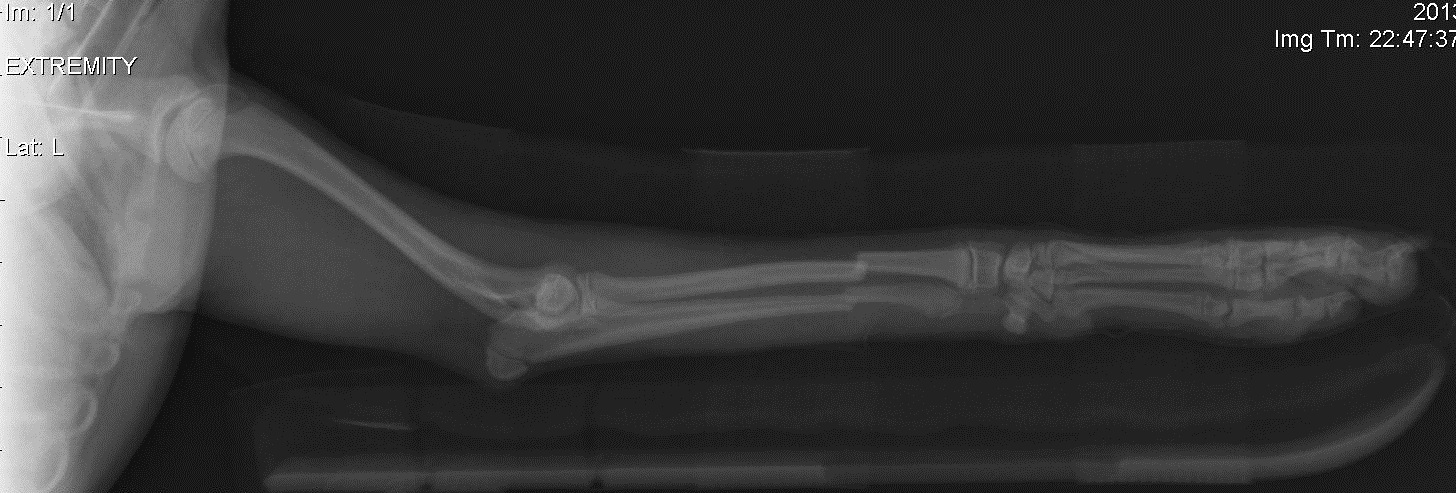

По умолчанию Щенок сломал ногу - что делать?

Щенок той-пуделя, 5 месяцев, вес 1.5 кг, прыгнула с высоты меньше метра и получила закрытый перелом обеих лучевых костей на передней лапе. У ветеринара мы были уже через полчаса. Ветеринар наложил лангету, но на снимке кости не совмещены идеально. Кости настолько маленькие, что без операции, думаю, лучше совместить их не удастся. По словам ветеринара, такого совмещения должно быть достаточно, чтоб кости срослись, и операцию можно не делать. Я понимаю, что он профессионал, но мне до этого доводилось иметь дело с некомпетентными ветеринарами (не этим), так что хочется услышать мнения. Делать операцию и мучить собаку еще одним наркозом, или надеяться, что заживет и так? Если можно, пишите, ветеринар вы, или просто владелец.

Я так понял, что ветеринар, который ставил гипс, либо не умеет делать такие операции, либо у них в клинике нет для этого оборудования (что странно, так как это что-то вроде круглосуточного ветеринарного травм-пункта). Поэтому не знаю, какой ему был резон так говорить. Есть опасения, что в других клиниках тут же начнут продавать свои услуги по операции, даже если она не нужна.

Вот снимки. Первый до, второй и третий после. Спасибо.

Sabut, Да, такой перелом без остеосинтеза - накостного (пластина) или внутримедуллярного (спица) - трудно иммобилизовать. Так как нога сейчас сложена - кости скорее всего срастутся если нога неподвижна, но лапа останется коротковатой и кривоватой. С другой стороны, делать остеосинтез собаке в полтора кг весом - трюк ещё тот... должен делать оч. хороший специалист (Вы где территориально?).

Также, чем кормите собачку? Либо она очень неудачно прыгнула, либо слишком хрупкие кости, что бывает связано с рационом или генетическое.

Все более убеждаюсь в третьем подряд опыте некомпетентного ветеринара. Я запостил этот вопрос на несколько форумов. Все в один голос твердят, что так оставлять нельзя. Послал фотки местному ортопеду - тот же ответ. Назначили операцию на завтра.